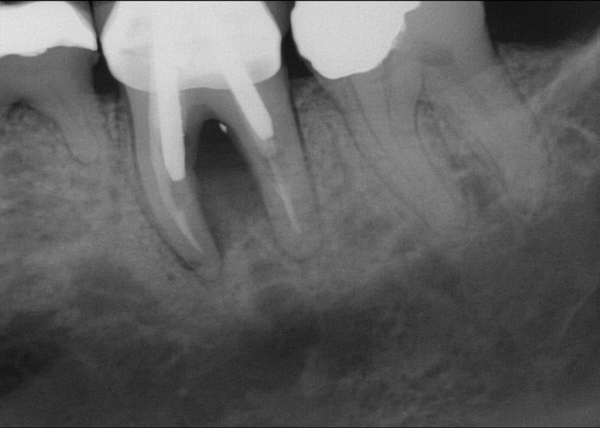

Fig 15. (Case 3) Radiograph of tooth No. 19, which had a hopeless prognosis.

Figure 15

Fig 16. Radiograph of extraction socket. Buccal and lingual plates were defective.

Figure 16